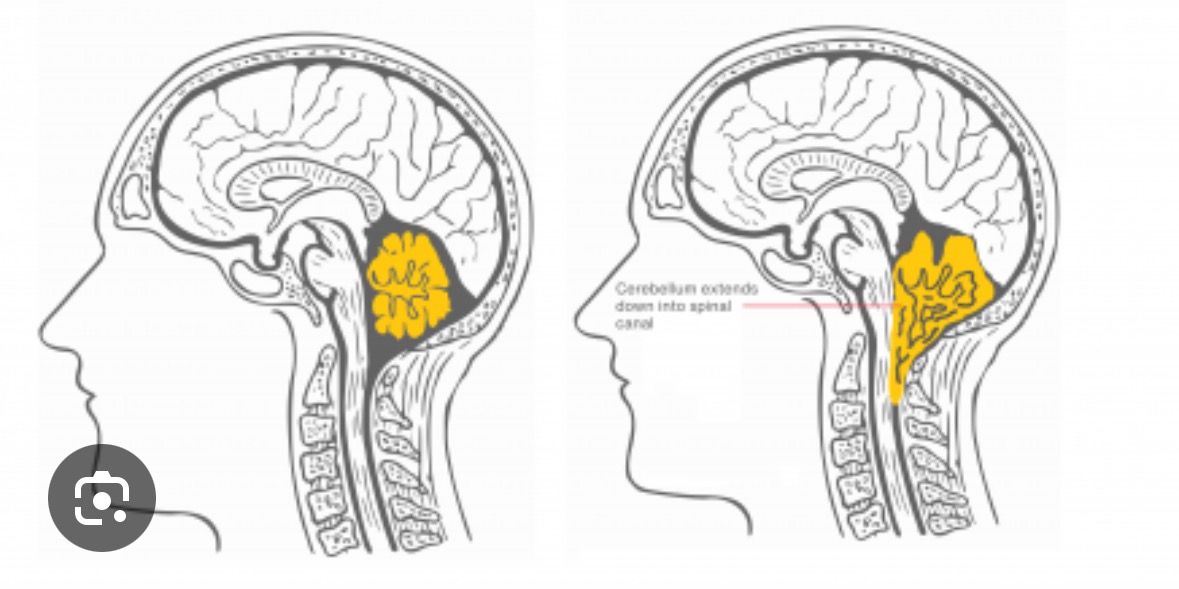

My name is Melissa, and I am facing a life-changing challenge due to Chiari malformation—a condition where brain tissue extends into the spinal canal because of a misshapen or smaller skull. This causes my brain to be pressed downward, leading to severe and frequent migraines. I experience around 22 migraines each month, many of which are so intense that I am unable to function. This has made it incredibly difficult to be present for my family and to keep up with my job. The pain and exhaustion are constant, and it has taken a toll on every aspect of my life.

I am preparing for brain surgery to address this condition. The process is complicated by a goiter on my thyroid, so I am currently waiting for a thyroid ultrasound before my surgery date can be set. I will know more about the timing after my appointment on August 11th. The funds raised will help cover my medical bills and support me during my recovery, which could require up to six months away from work. Any support will make a meaningful difference as I navigate this difficult journey and focus on healing for myself and my loved ones.